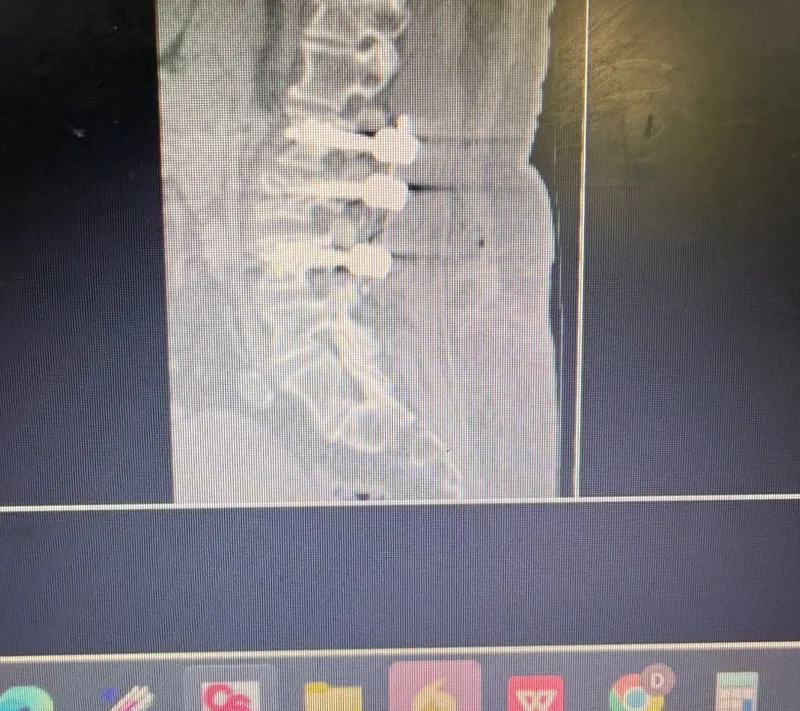

La tomografía computarizada (TAC) de María mostró una fractura de la columna vertebral lumbar con compromiso de la estabilidad. Pero el verdadero desafío no era solo la fractura — era la osteoporosis severa que debilitaba toda la estructura ósea de su columna.

La artrodesis de columna consiste en fusionar vértebras para darle estabilidad a un segmento dañado. Se insertan tornillos pediculares a través de los pedículos vertebrales y se conectan con barras metálicas que inmovilizan el segmento fracturado.

Pero en pacientes con osteoporosis severa como María, se necesita un paso adicional: cementar los tornillos. Antes de insertar cada tornillo, se inyecta cemento óseo (polimetilmetacrilato o PMMA) en el cuerpo vertebral. Esto: